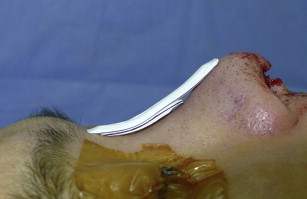

Although costal cartilage is difficult to harvest and is associated with serious donor site morbidities such as pneumothorax, as well as the problem of implant warping, it is the most useful autologous cartilage for thick-skinned primary cases, which require substantial augmentation, or in patients who have experienced complications with alloplastic implants ( Figs. 6 and 7 ).